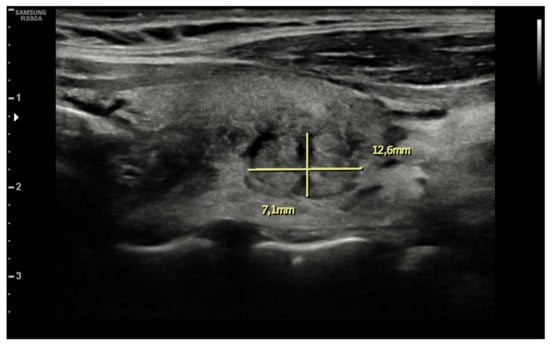

| Ultrasound findings at presentation | Asymmetric thyroid enlargement with two hypoechoic areas with no internal vascularity on right thyroid lobe | Diffuse thyroid enlargement with hypoechoic areas with heterogeneous echotexture and no evidence of increased vascularity | Diffuse enlargement of thyroid gland with hypoechoic nodules with hyperechoic shoots (micronodular pattern) without increase in vascularity | ||||||||||||||

| Ultrasonographic findings | ||||

| Hypoechoic areas | 8 (80%) | 3 (75%) | 5 (83.3%) | 1 |

| Heterogeneous echotexture | 4 (40%) | 1 (25%) | 3 (50%) | 0.571 |

| Reduced blood flow at Doppler-US | 6 (60%) | 1 (25%) | 5 (83.3%) | 0.119 |